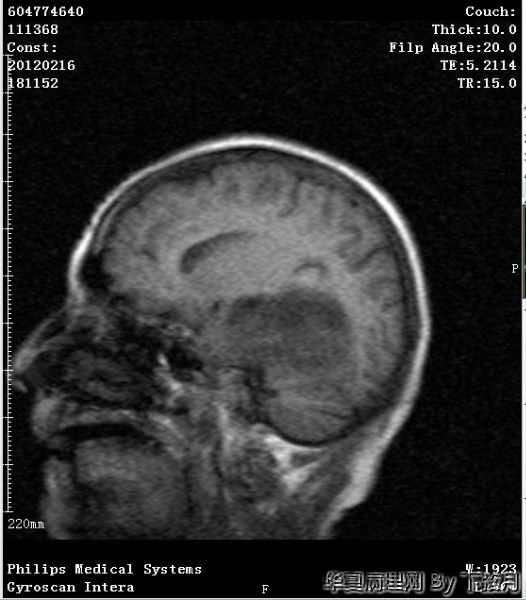

左侧颞叶及胼胝体膝部占位

左侧颞叶及胼胝体膝部占位图14

左侧颞叶及胼胝体膝部占位图15

粘液型乳头状室管膜瘤:好发于年轻人,几乎毫无例外位于圆锥-马尾终丝区。组织学Ⅰ肿瘤细胞围绕血管粘液样间质为轴心,排列成乳头状为特点。本例是老年人,位于左侧颞叶及胼胝体膝部,年龄和位置不太相符。另外本例Ki-67指数有点高。有点疑惑

从图1可见肿瘤似位于脑皮质外围,有粘液背景,部分如脊索瘤样,倾向于脊索瘤样脑膜瘤。